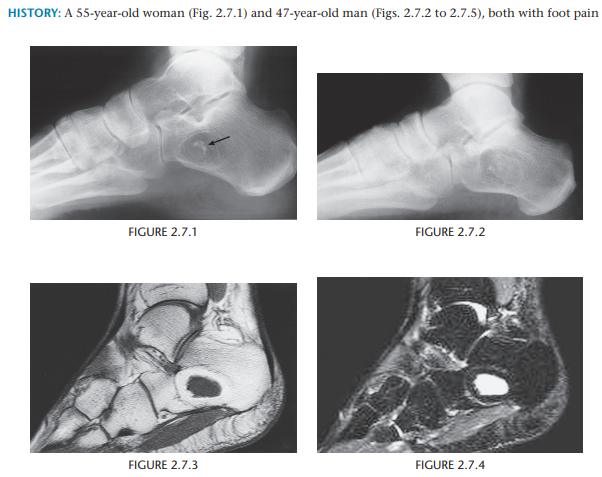

Intraosseous lipoma

A lytic lesion with a thin, sclerotic border and central calcification (especially within the calcaneus) represents an intraosseous lipoma until proven otherwise.

Ave size = 4 cm